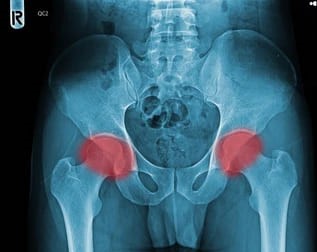

골반괴사는 골반 주위의 뼈가 혈액 공급을 충분히 받지 못해 괴사 하는 질병입니다. 이로 인해 뼈가 약화되고 통증이 동반됩니다. 이때 음식은 어떻게 골반괴사 예방과 치료에 도움이 될까요? 뼈 건강을 유지하는 데 필수적인 영양소를 음식으로 섭취함으로써 골반괴사를 예방하거나 증상을 완화할 수 있습니다. 칼슘, 비타민 D, 마그네슘 등 뼈 건강에 좋은 영양소를 충분히 섭취하는 것이 중요합니다. 이러한 영양소는 음식으로 쉽게 얻을 수 있어서 약에 의존하지 않고도 건강을 관리 수 있습니다.